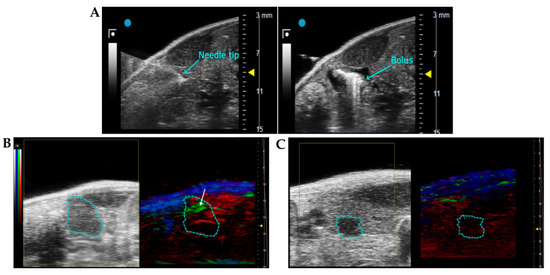

3.3.1. Penetration of the scDb hERG1/β1 into the Tumour Masses of an Orthotopic Xenograft PDAC Mouse Model: Evidence with Photo Acoustic (PA) Imaging